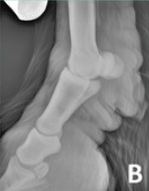

RX Images

In the 2013 Verena K. Affolter (U.C.Davis) study into CPL in Draft Horses there is a brief list of other potential diagnostics including lymphoscintigraphy and lymphangiogram. These procedures are expensive, invasive and unnecessary. Radiographs will show the extent of the folds but again are a surplus cost and show nothing that we can’t already see and feel, with regards to the CPL.